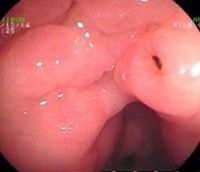

1.慢性浅表性胃炎又称慢性单纯性胃炎胃粘膜最常见的病变之一,国内胃镜检出率高达20%~40%,以胃窦部常见;胃镜见胃粘膜:胃粘膜充血、水肿,呈淡红色,可伴点状出血及糜烂,表面可有灰黄色或灰白色粘液渗出物覆盖;显微镜示:病变位于粘膜浅层;